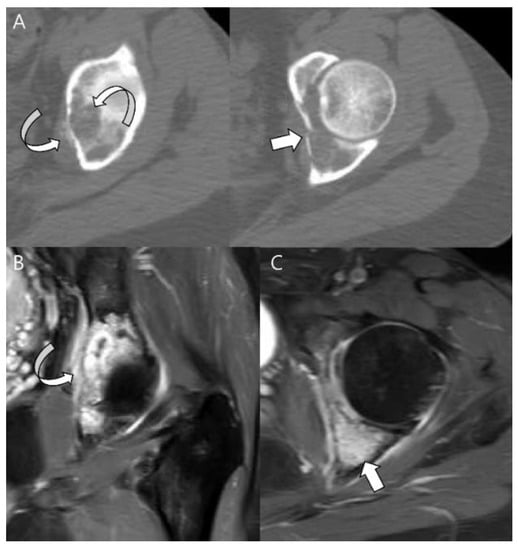

- Kawaguchi, S.; Wada, T.; Nagoya, S.; Ikeda, T.; Isu, K.; Yamashiro, K.; Kawai, A.; Ishii, T.; Araki, N.; Myoui, A.; et al. Extraskeletal myxoid chondrosarcoma: A Multi-Institutional Study of 42 Cases in Japan. Cancer 2003, 97, 1285–1292. [Google Scholar] [CrossRef]

- Drilon, A.D.; Popat, S.; Bhuchar, G.; D’Adamo, D.R.; Keohan, M.L.; Fisher, C.; Antonescu, C.R.; Singer, S.; Brennan, M.F.; Judson, I.; et al. Extraskeletal myxoid chondrosarcoma: A retrospective review from 2 referral centers emphasizing long-term outcomes with surgery and chemotherapy. Cancer 2008, 113, 3364–3371. [Google Scholar] [CrossRef]

- Antonescu, C.R.; Argani, P.; Erlandson, R.A.; Healey, J.H.; Ladanyi, M.; Huvos, A.G. Skeletal and extraskeletal myxoid chondrosarcoma: A comparative clinicopathologic, ultrastructural, and molecular study. Cancer 1998, 83, 1504–1521. [Google Scholar] [CrossRef]

- Aigner, T.; Oliveira, A.M.; Nascimento, A.G. Extraskeletal myxoid chondrosarcomas do not show a chondrocytic phenotype. Mod. Pathol. 2004, 17, 214–221. [Google Scholar] [CrossRef] [PubMed]